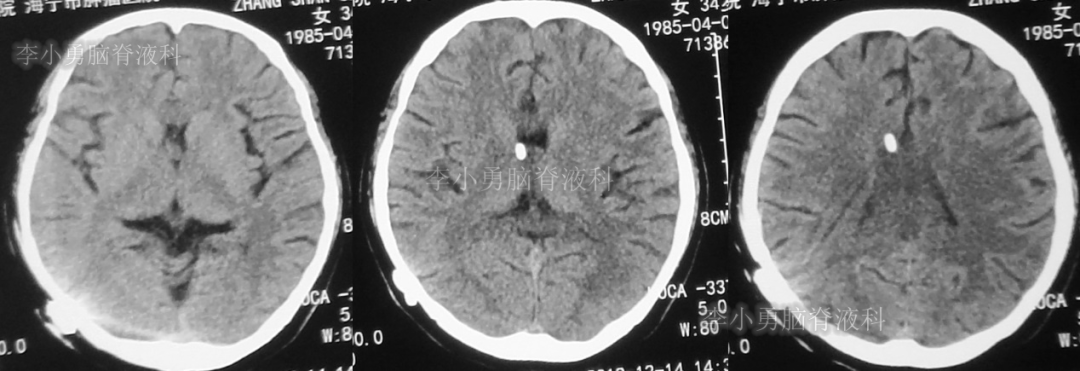

患者于2018年1月29日,突发头痛、头晕、恶心、呕吐,并高热40度。在当地医院门诊输入4天抗生素后发热缓解,但出现了双眼不能上视(眼球不能向上看)。5天后即2018年2月3日,在当地的第1家医院:浙江省海宁市某医院行头颅CT(图-1)发现脑室扩张,当地医院诊断为“梗阻性脑积水”。

图-1:2018年2月3日头颅CT